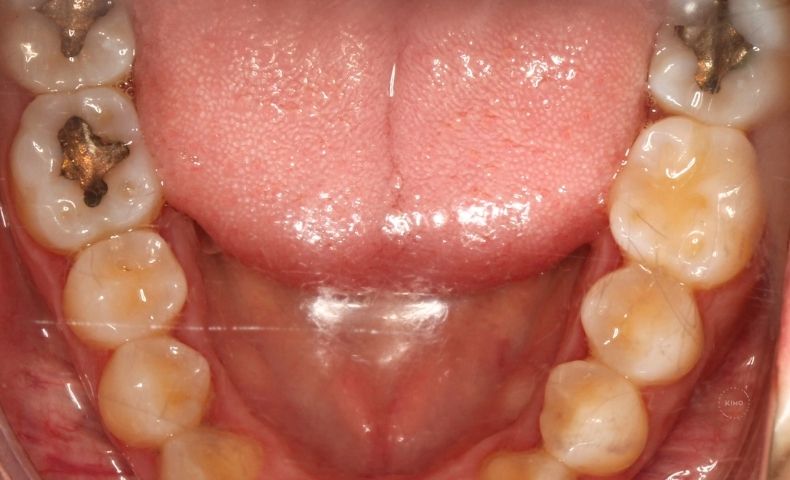

Problemas dentales y periodontales

No podemos olvidar las causas puramente dentales:

- Caries profundas.

- Infecciones o abscesos.

- Problemas en la pulpa dental.

- Enfermedades de las encías.

En estos casos, el dolor suele estar más localizado en un diente o en una zona concreta de la boca, aunque también puede irradiarse hacia la cara o el oído.